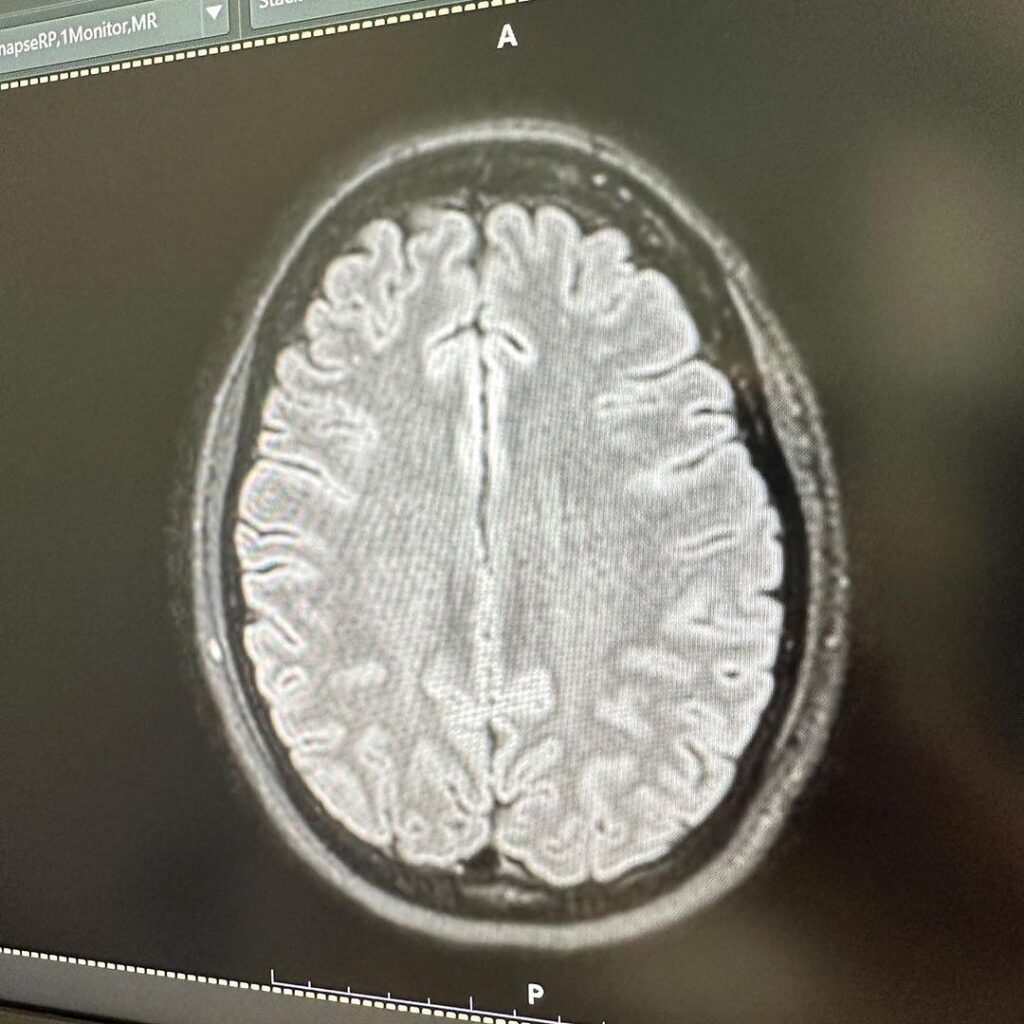

แต่ล่าสุดเจ้าตัวโพสต์ภาพสแกนสมอง หลังเข้ารับการรักษา ทำ MRI สมอง เนื่องจากมีอาการปวดหัวจัด จนกังวลใจคิดไปไกลกลัวจะเป็นเนื้องอก แต่สุดท้ายผลตรวจพบว่า เป็นไมเกรน ทำเอาเจ้าตัวโลงอก

“MRI สมอง เพราะปวดหัวมาก สรุปเป็นไมเกรน 😮💨 😵💫 นึกว่าเป็นเนื้องอก ลุ้นเเทบตาย โล่งอก😮💨 คุณหมอให้ยาฉีดที่ขาเเต่เป็นยาฉีดสำหรับไมเกรน ดีขึ้นเลย 💉เเต่ต้องฉีดต่อเนื่อง3-6เดือน ดีจังไม่ต้องทนปวดกินยาเเล้ว☺️”